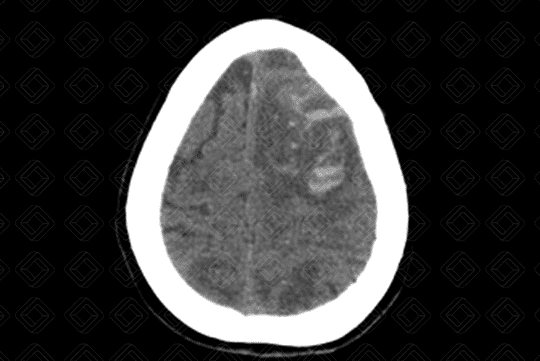

Descrição das imagens: Paciente masculino, 68 anos, com hemorragia intracraniana causada por rotura de um aneurisma da artéria cerebral média esquerda. Observa-se a presença de áreas espontaneamente densas (sangue), intraparenquimatosas, no lobo frontal e parietal esquerdos (setas vermelhas), causando discreto desvio da linha média contralateralmente. Nota-se ainda hipodensidade periférica devendo representar edema.

• Tomografia computadorizada do crânio: Deve ser feita avaliando sua densidade, seu volume, sua localização e sua relação com as estruturas circunjacentes. Lembrar que a densidade compatível com sangue na tomografia computadorizada encontra-se em torno de 50 a 70 UH. Permite ainda avaliar se há efeito compressivo ou desvio de linha média, por exemplo. A aparência da hemorragia intracraniana não complicada na tomografia computadorizada é relativamente direta e de fácil percepção (Figura 1);